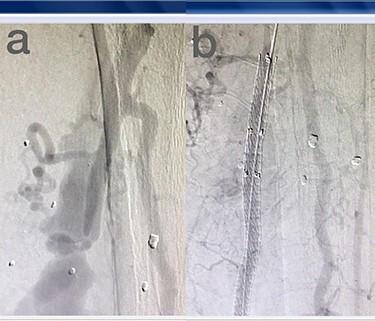

穿透性血管损伤的血管内治疗

Endovascular treatment of penetrating vascular injuries.

Endovascular treatment of vascular injuries has resulted in reduced operating time, blood loss, hospital mortality and sepsis. The purpose of this study was to evaluate the success and complication rate of the endovascular management of penetrating peripheral vascular injuries during 5 years. In this observational study, the clinical records and imaging features of 22 penetrating trauma injuries of 276 penetrating vascular trauma patients (8%), which were repaired using endovascular stent-grafts or coil embolization, between April 2013 and August 2018, included in the study. The median age of patients was 43 years (Range, 20-78 years). There were 17 stab wounds (77.3%), 2 shotgun war remnants (9.1%) and 2 iatrogenic post-surgical lesions. Eleven stent-grafts (50%) and nine coil embolizations (40.9%) were deployed. Endovascular interventions in the management of peripheral vascular injuries can be efficient in definitive repair, damage control and hemorrhage control in severely ill trauma patients.

血管损伤的血管内治疗已使手术时间、失血量、医院死亡率和败血症发生率降低。本研究的目的是评估5年间穿透性周围血管损伤的血管内治疗的成功率和并发症发生率。在这项观察性研究中,纳入了2013年4月至2018年8月期间276例穿透性血管创伤患者(8%)中22例穿透性创伤损伤的临床记录和影像特征,这些损伤采用血管内支架移植物或弹簧圈栓塞进行修复。患者的中位年龄为43岁(范围20 - 78岁)。有17处刺伤(77.3%)、2处散弹枪战争遗留伤(9.1%)和2处医源性术后损伤。使用了11个支架移植物(50%)和9次弹簧圈栓塞(40.9%)。血管内介入治疗周围血管损伤在危重伤员的确定性修复、损伤控制和出血控制方面可能是有效的。